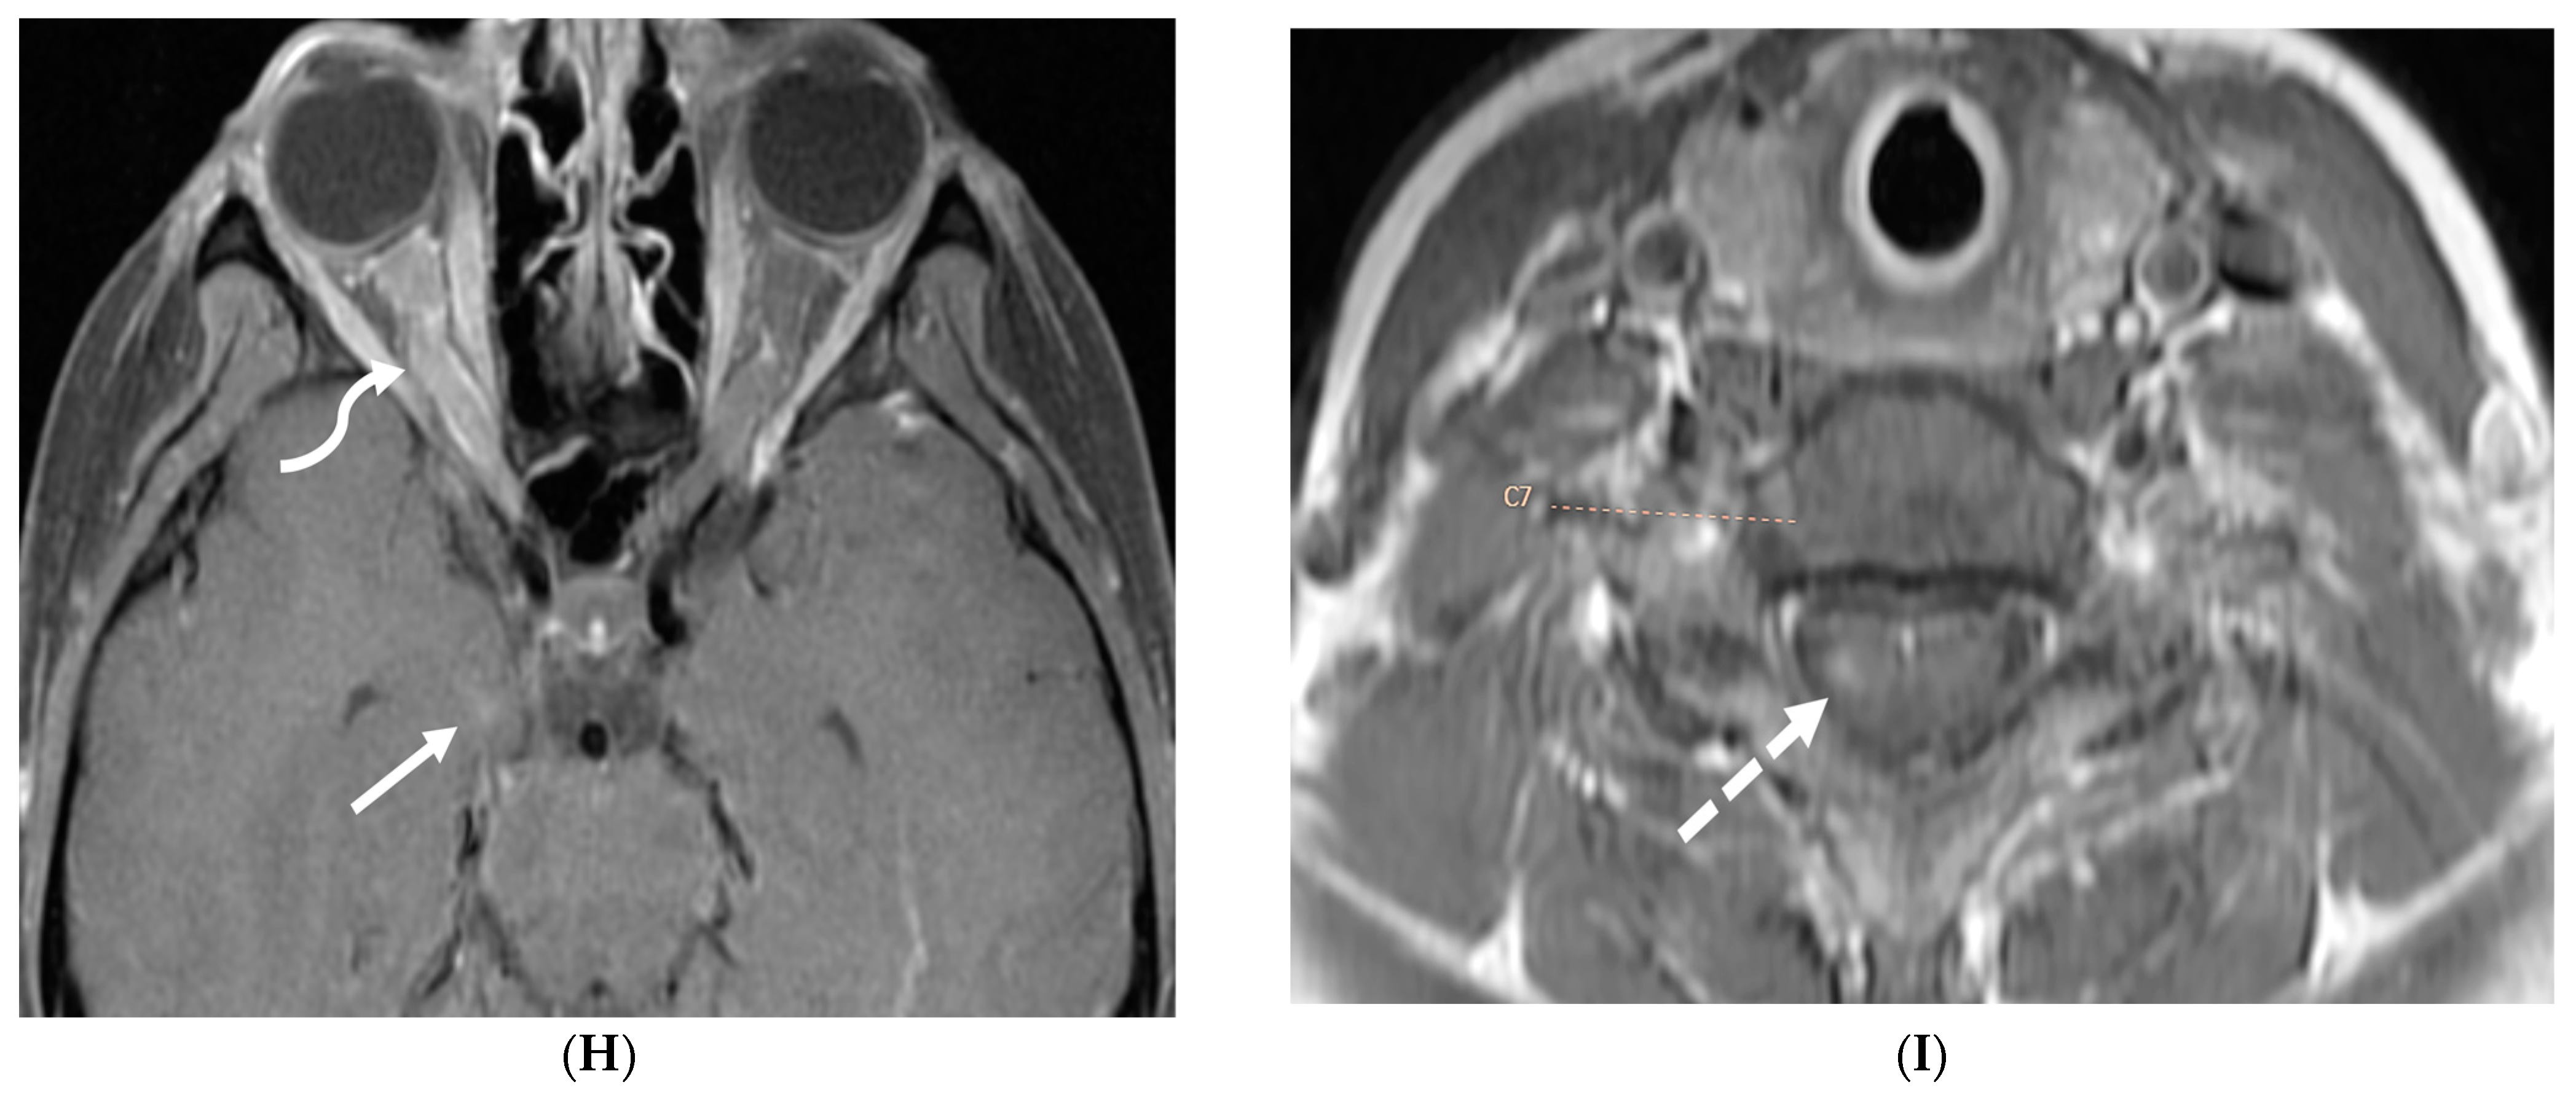

5.3. Anti-Myelin Oligodendrocyte Glycoprotein (MOG) Demyelination

Anti-MOG antibody associated demyelination (MOGAD) frequently presents as Acute Disseminated Encephalomyelitis (ADEM) in children and opticospinal involvement in young adults [105]. Bilateral but asymmetric T2 hyperintense lesions occur in thalamus, pons and cerebellar peduncles are common in children [106]. Optic nerve involvement typically presents as a long segment with anterior predominance, in contrast to the posterior predominance seen in Neuromyelitis Optica Spectrum Disorders (NMOSD) and the short segment involvement characteristic of Multiple Sclerosis (MS) [106].

LME has been shown to present early in the disease course and is much more common in children (33%) compared to adults (8%) [107]. Gadde et al. found that 8% of pediatric MOG antibody-associated demyelination cases had only LME without any other central nervous system manifestation. LME when present can be particularly helpful in differentiating from NMOSD [106]. Furthermore, Valencia-Sanchez et al. reported a significant association between LME and cerebral cortical encephalitis in MOG antibody-associated disease. This finding suggests that LME may be an important marker for cortical involvement and potentially more severe disease (Figure 21) [108].

Figure 21.

Sagittal T2 (A,B), axial FLAIR (C), axial T2 cervical spine (D) at the level of C7 vertebral body and Axial T2 orbits (E): 12-year-old girl presented with right focal motor seizure and left temporal lobe slowing on electroencephalogram (EEG). Right eye vision loss and irritability. Ill-defined areas of signal abnormalities are identified within the RIGHT mesial temporal lobe and bilateral medulla (white arrows). FLAIR hyperintensity is identified on the left central sulcus (black arrow). Small focus of signal abnormality is seen on the right side of the cord at the 7th cervical vertebra (C7) (dashed arrow). There is also bilateral papilledema (arrowheads). Post contrast axial T1 (F,G), axial T1 orbits (H) and axial T1 cervical spine at C7 (I): Asymmetric LME (black arrows) predominantly involving the left cerebral hemisphere, with minimal right parietal involvement is seen. Ill-defined enhancement in the right mesial temporal lobe, and right greater than left medulla (white arrows) corresponds to the signal abnormality. There is right greater than left, optic nerve enhancement (curved arrow). Single small enhancing lesion in the spinal cord on the right at the level of C7 corresponds to the signal abnormality (dashed arrow). Features favor a demyelinating process. MOG antibodies were positive at 1:20 in keeping with Myelin oligodendrocyte glycoprotein (MOG) antibody disease (MOGAD).